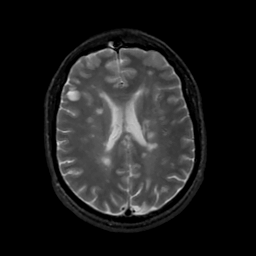

MR Study #10, April 28, 1991 -- Slice #31